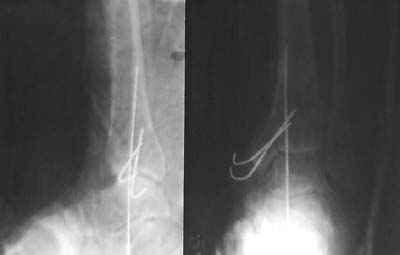

После совместного осмотра с зав.отд.микрохирургии пациент госпитализирован в клинику микрохирургии. Дежурными врачами этой же клиники принято решение сохранить конечность, выполнены ПХО, фиксация спицами, гипсовая иммобилизация. Результаты - см.приложение.